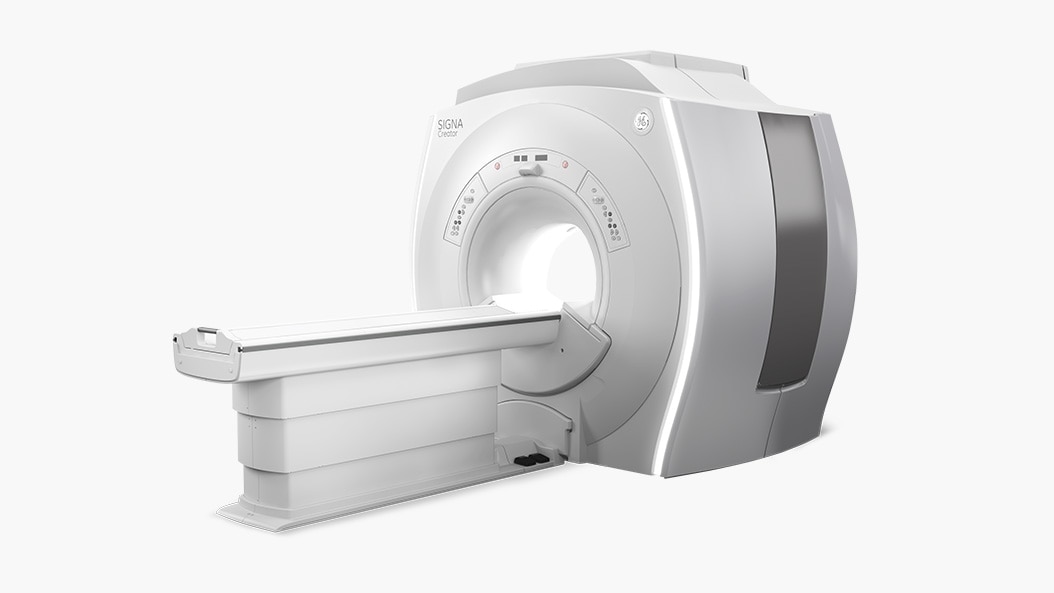

GoldSeal offers affordable high-performance MR systems to help you make accurate diagnoses. The combination of clinical applications and technology improve imaging, while helping you manage data productively. GoldSeal refurbished MR systems help put leading-edge imaging capabilities within your budget.